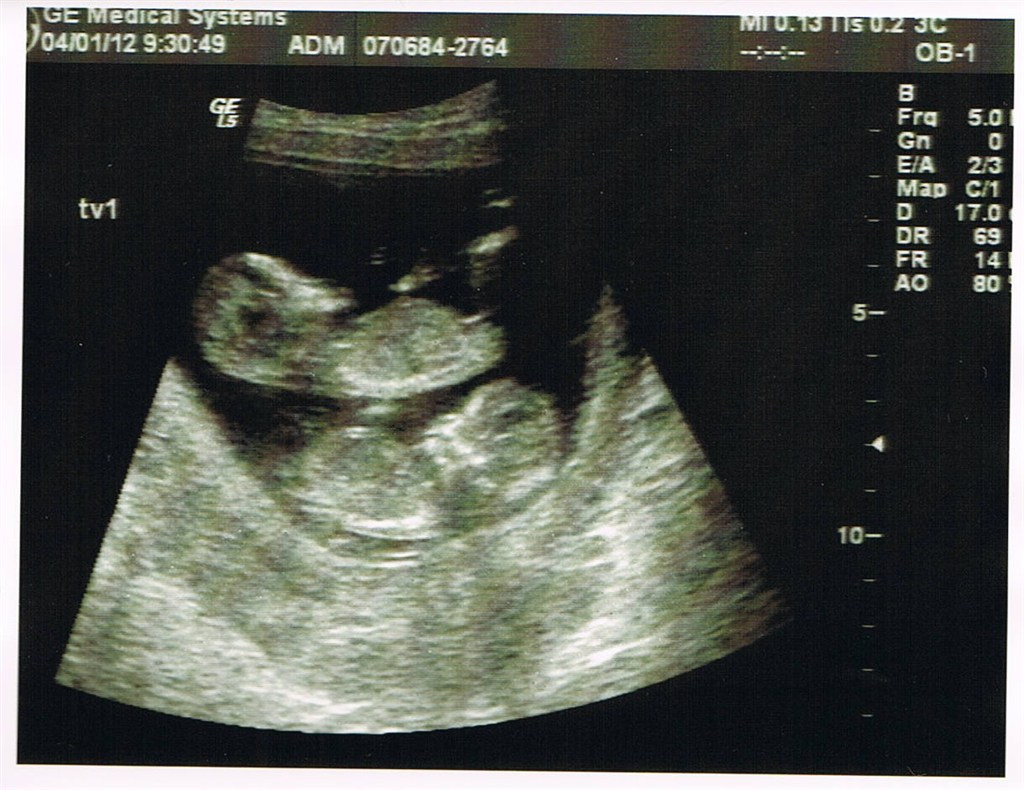

fine tal på 1:2990 på begge tvillinger og jeg blev rykket frem til at være 13+4

De fastatte nu endelig til at være enæggede tvillinger med hver deres foterhinde men samme moderkage. Dette skræmmer mig lid da det betyder scanninger hver 14 dag indtil termin og en masse undersøgelser.....